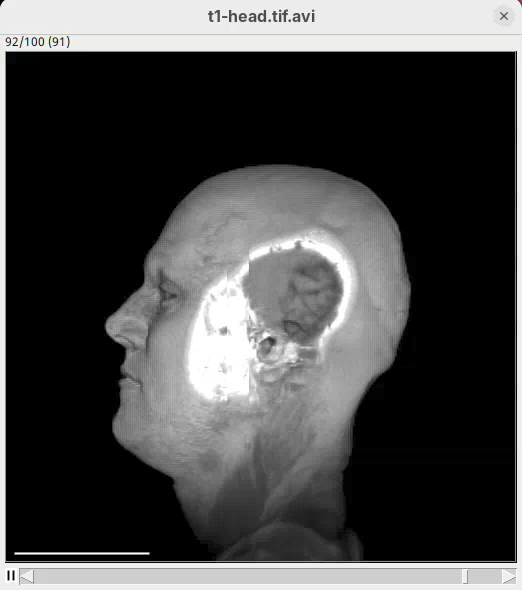

Animate cropping

Let’s add a couple more commands below our rotation sentence. We want that, after the 360 degree rotation, the animation slices through the head to show the tissues inside. For that, we can change the cropping parameters to control the position of the bounding box during the animation.

- After the first sentence, write the two commands as shown below:

From frame 0 to frame 35 rotate by 360 degrees horizontally

From frame 36 to frame 71 change channel 1 bounding box min z to 60

From frame 72 to frame 99 change channel 1 bounding box min z to 0- Press

Run.

The script is saying to rotate 360 degrees horizontally, as before, set the Z range minimum to 60 (roughly halfway through the sample) for about 30 frames, and then set the Z range minimum back to 0 in the subsequent 30 frames. And that’s what we get.